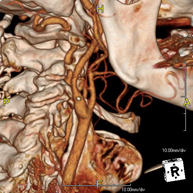

Prueba radiológica que consiste en obtener imágenes del hueso peñasco del temporal (oído interno, medio y externo) de alta definición anatómica mediante el empleo de un equipo de TC (Tomografía Computarizada). Indicaciones: pérdida de audición súbita o crónica, cuadros vertiginosos, mareo, malformaciones congénitas. - Angio – TC Troncos Supraaórticos

Prueba radiológica que consiste en obtener imágenes de las arterias carótidas del cuello de alta definición anatómica mediante el empleo de un equipo de TC (Tomografía Computarizada) y la inyección de contraste intravenoso. Posteriormente, las imágenes son reconstruidas en tres dimensiones (3D). Indicaciones: accidente vascular cerebral agudo, accidente vascular transitorio, soplo carotídeo. - TC Columna cervical

- Angio-TC-Troncos Supraaórticos

Prueba radiológica que consiste en obtener imágenes de las arterias carótidas del cuello de alta definición anatómica mediante el empleo de un equipo de TC (Tomografía Computarizada) y la inyección de contraste intravenoso. Posteriormente, las imágenes son reconstruidas en tres dimensiones (3D). Indicaciones: accidente vascular cerebral agudo, accidente vascular transitorio, soplo carotídeo. - Angio TC- aorta toràcica